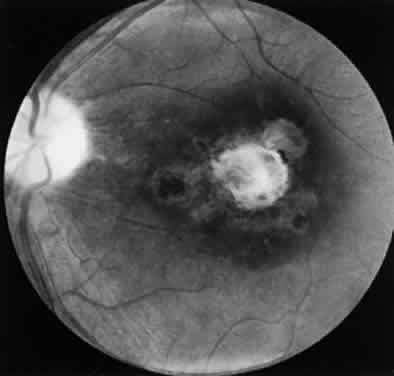

Ocular toxoplasmosis most commonly presents as a focus of necrotizing retinitis (Fig. 7) involving the inner layers of the retina and associated with a whitish fluffy lesion surrounded by retinal edema.6,59 Cells are seen in the vitreous overlying the lesion. The focus of retinitis may be large (Fig. 8) or small (Fig. 9). The retina is the primary site for the multiplying parasites, whereas the choroid and sclera may be the sites of contiguous inflammation. When the choroid is involved by the inflammatory reaction, the lesion is referred to as retinochoroiditis. The organisms are rarely seen in the choroid. The retinal lesion may be small and single or large and multiple and may reach several disc diameters in size. Large granulomas in the posterior segment of the eye frequently are seen in patients with ocular toxoplasmosis (Fig. 10). This is associated with extensive and marked vitreous reaction that precludes visualization of the retina, and the granuloma appears as a yellowish mass surrounded by a red reflex. Punctate outer retinal involvement may be seen in some patients with toxoplasmosis.60 These appear as multifocal, gray-white lesions in the deep retina and at the level of the retinal pigment epithelium accompanied by no overlying vitreous reactions. The lesions may resolve to form fine, granular white dots. This is the earliest finding seen in the rabbit models of ocular toxoplasmosis after the injection of Toxoplasma organisms in the suprachoroidal space. The lesions in the animal model may start as deep outer retinal punctate lesions that later involve the inner layers of the retina and cause the typical focus of retinochoroiditis. Involvement of the macular area is common in patients with congenital toxoplasmosis, and exudative retinal detachment may occur in severe cases. Clumps of inflammatory cells may be seen in the vitreous or over the detached posterior vitreous face. The focus of retinitis may be a manifestation of congenital toxoplasmosis or may be associated with or follow an episode of acquired systemic toxoplasmosis. Patients presenting with recurrent toxoplasmic retinochoroiditis usually are in the second or third decade, but the disorder may occur at any age. Healing of the retinitis is associated with a decrease in retinal edema and flattening of the lesion with evidence of scar formation surrounded by variable amounts of pigment (Fig. 11). The lesion may appear as a punchedout scar with underlying sclera resulting from extensive retinal and choroidal necrosis surrounded by pigment proliferation (Fig. 12), it may become a conglomerate or proliferated retinal pigment cells (Fig. 13), or it may be small and appear as a pigment clump in the retina. The retinochoroiditic scar may harbor the Toxoplasma cysts. Healing also is associated with decrease in the vitreous cells and improvement in visual acuity. Immunologic suppression is associated with recurrence of retinochoroiditis (Fig. 14). Recurrent toxoplasmic retinitis frequently appears as “satellites” or occurs adjacent to a previous scar. Old, inactive lesions often appear to be a conglomeration of previous multiple inflammatory foci (see Fig. 13).

Fig. 12. Typical punched-out Toxoplasma retinochoroiditic scar surrounded by pigmentation. The central whitish area is the sclera and results from extensive necrosis of the retina and choroid. Toxoplasma cysts may remain viable in the retina throughout life.

Fig. 13. Multiple retinochoroiditic scars with pigment proliferation seen in the retina of a 28-year-old woman who had three previous episodes of Toxoplasma retinochoroiditis.